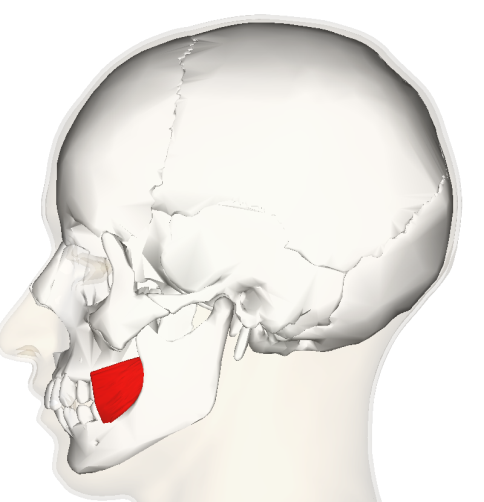

30.  ?  The coloured structure shows

Explanation

The correct answer is Buccinators. The question is asking for the name of the coloured structure shown in the image. The options provided are Zygomaticus major, Zygomaticus minor, Buccinators, and Omohyoid. Based on the options given, the correct answer is Buccinators.